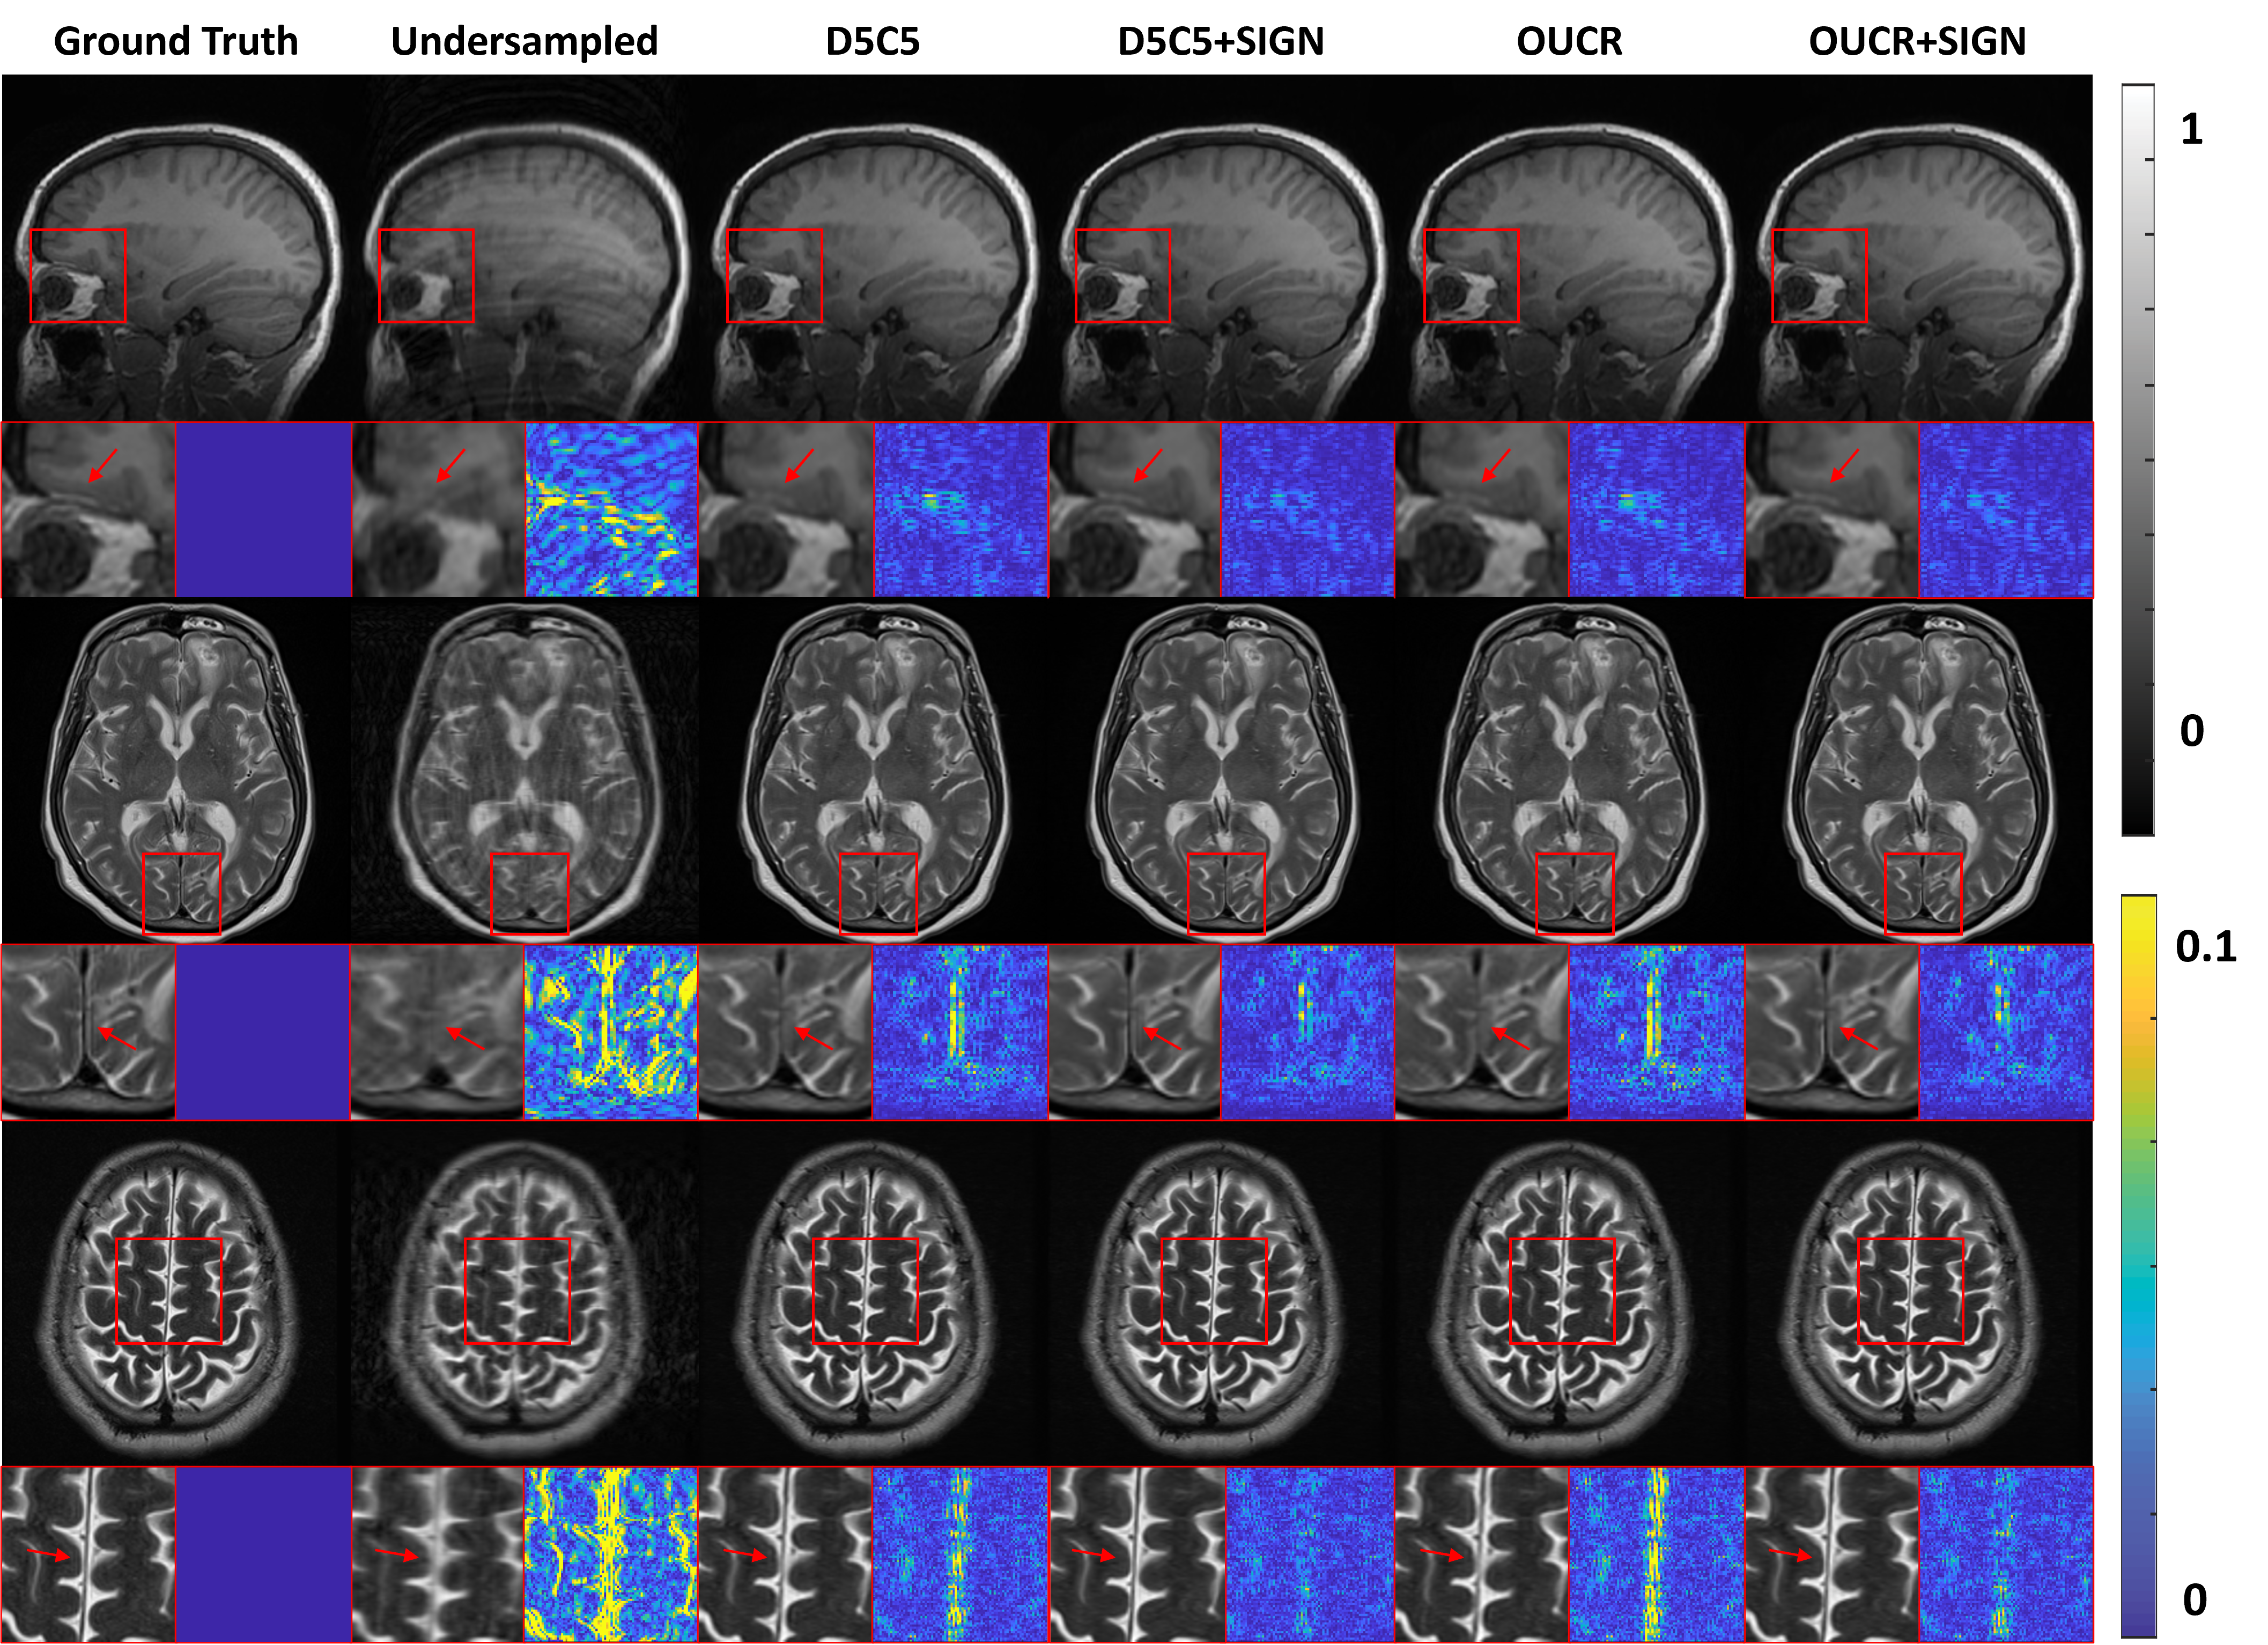

Fig. 5 shows the examples of reconstructed brain images under 4×\times acceleration with different methods. The first column is the fully-sampled images and the second column represents the undersampled images, which are blurry and full of artifacts. As shown in the third column, D5C5 can reconstruct the images. In the forth column, D5C5++SIGN further improves the images with more detailed information preserved, as pointed by the arrows. Similar trend can also be observed by comparing the fifth column (OUCR) and the sixth column (OUCR++SIGN). OUCR with the SIGN inserted in the network recovers the images with higher visual fidelity.

Refer to caption

Figure 5: The reconstructed brain images under 4×\times acceleration with different methods.